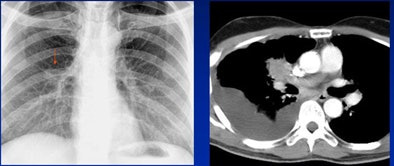

| Decision-making error: Lung mass (arrow, left) was called as a pulmonary artery. All images courtesy of Dr. Charles White. |